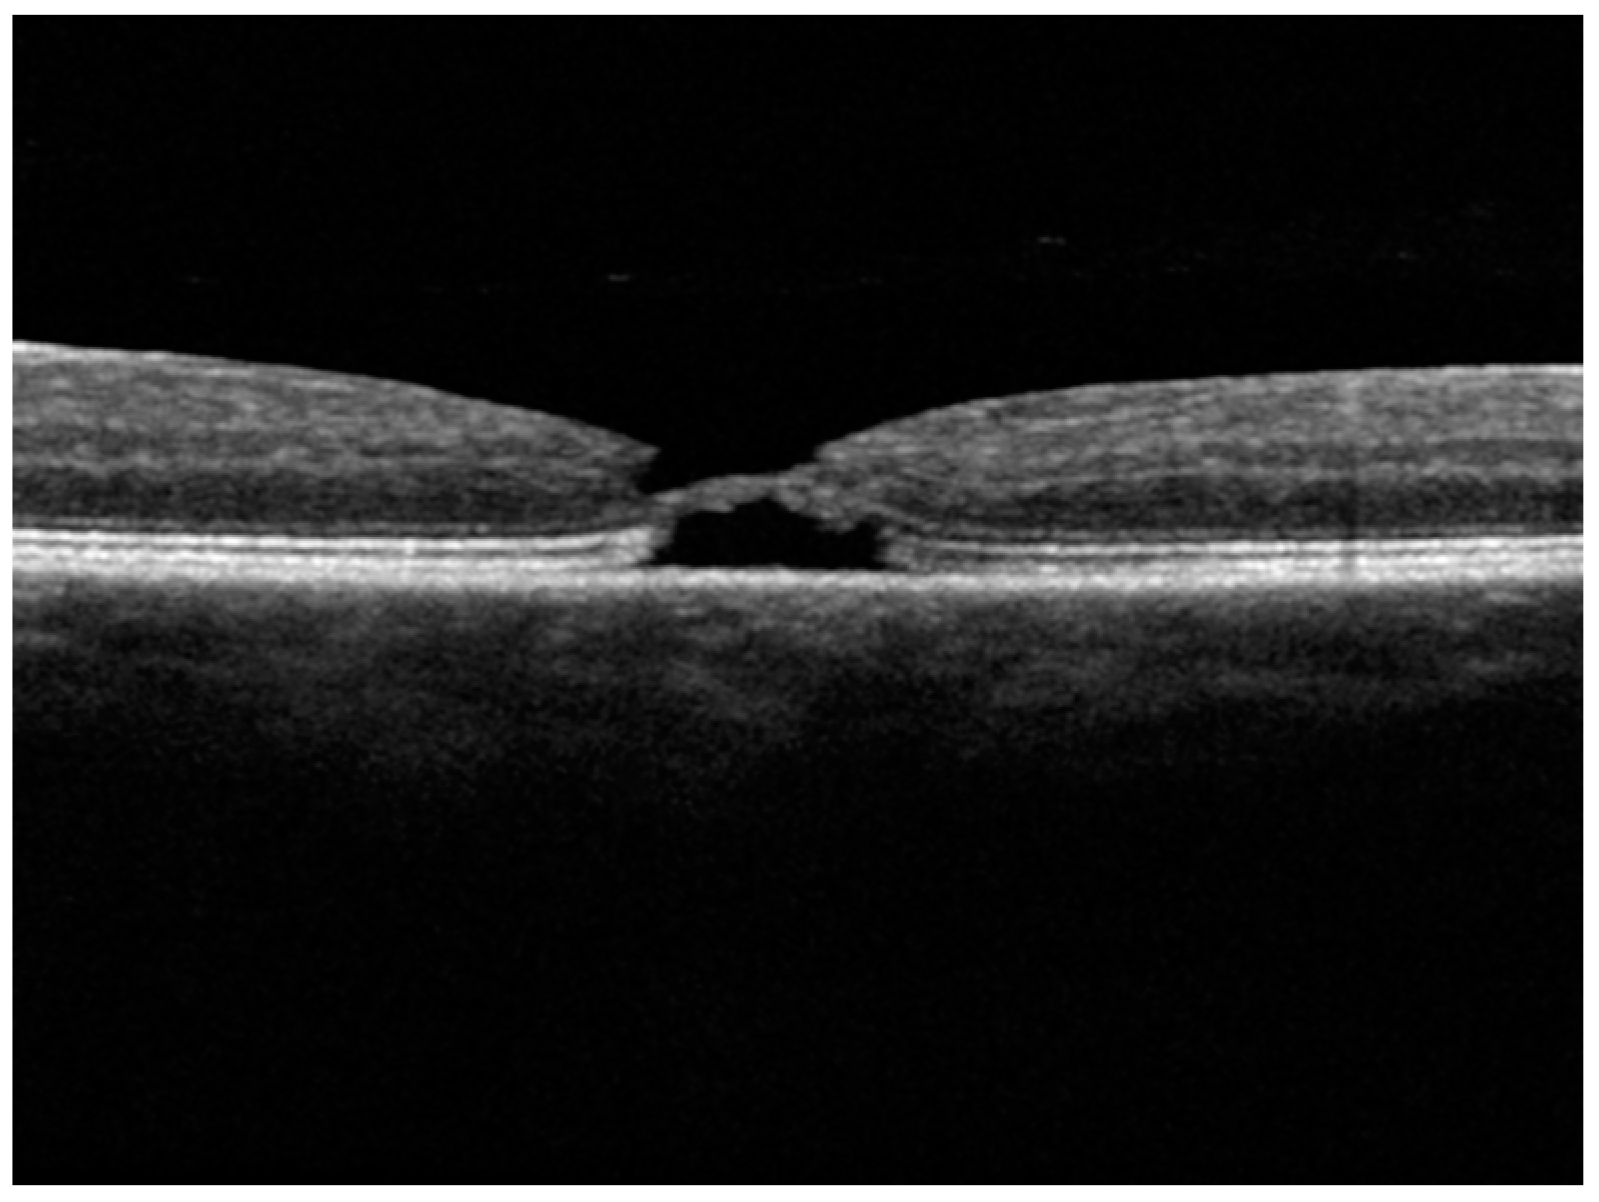

3.1.8. Patient 8, Right Eye

3.2. Analysis of Results